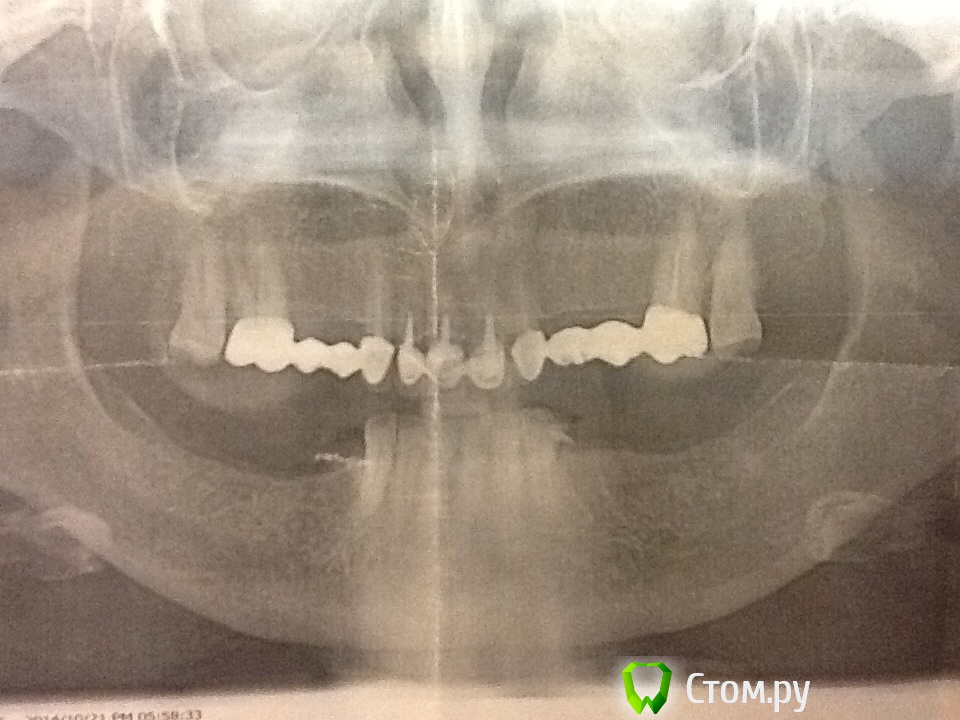

Evikrol Опубликовано 21 октября, 2014 Автор Поделиться Опубликовано 21 октября, 2014 (изменено) Завтра посмотрит хирург. Вроде уговорил на импланты. Хватит ли костной ткани?Улыбки нет. Глубокий прикус Изменено 21 октября, 2014 пользователем Evikrol Ссылка на комментарий

M@estro Опубликовано 21 октября, 2014 Поделиться Опубликовано 21 октября, 2014 Видя такой снимок-в первую очередь бы подумал об имаксе на нижние резцы.. 4 Ссылка на комментарий